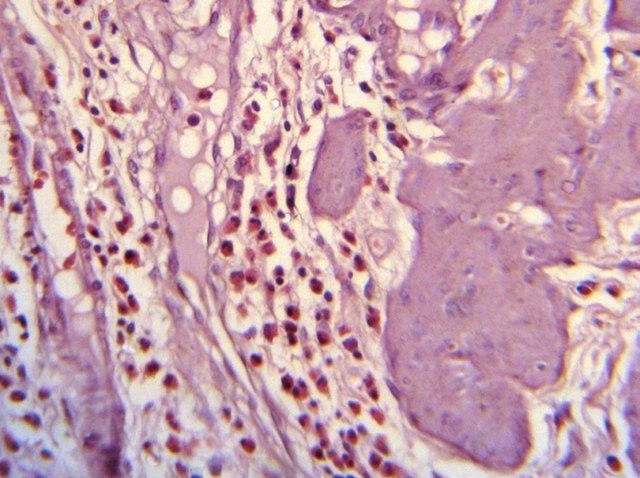

Patologi

Over 90 % av kroniske tilfeller er direkte forbundet med gallestein, som ved gjentatte anfall delvis blokkerer utførselsgangen og gir stadig tilbakevendende inflammasjon. Betennelsen fører over tid til at galleblæreveggen blir fortykket og stiv, med økt risiko for arrdannelse og i noen tilfeller vevsdød eller ruptur. I akutte, ubehandlede tilfeller kan tilstanden utvikle seg videre til perforasjon, alvorlig infeksjon (sepsis) og død.